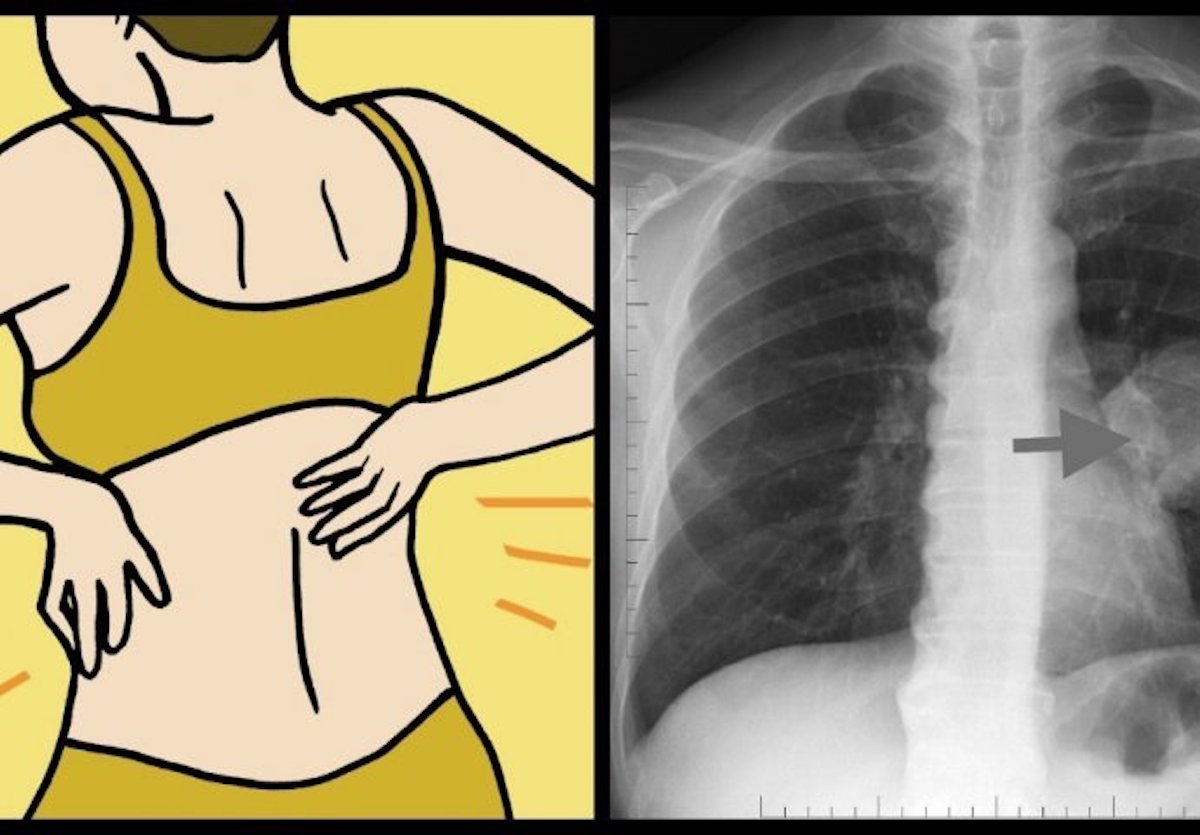

- Bol u prsima, ramenima, leđima i abdominalna bol

Čak kod 1 od 4 osobe bol u prsima se javlja kao prvi simptom raka pluća, osim toga javlja se bol u mišićima i napetost, te bol na području ramena, leđa ili abdomena.

Plućna embolija je poremećaj koji nastaj nakupljanjem zgusnute krvi u pulmonarnoj arteriji s posljedičnom opstrukcijom dotoka krvi u plućno tkivo.

Najčešći tip plućnog ugruška je tromb koji je obično potekao iz vene u nozi ili zdjelici. Ugrušci se proširuju u oba plućna krila u 65% slučajeva, u desno plućno krilo u 25%, te u lijevo plućno krilo u 10% slučajeva. Većina tromboembolusa nakuplja se u velikim ili srednjim pulmonarnim arterijama.